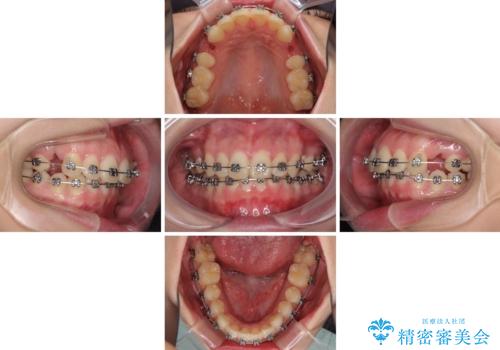

- メタルブラケット

- 3年1ヶ月

- 10-30回